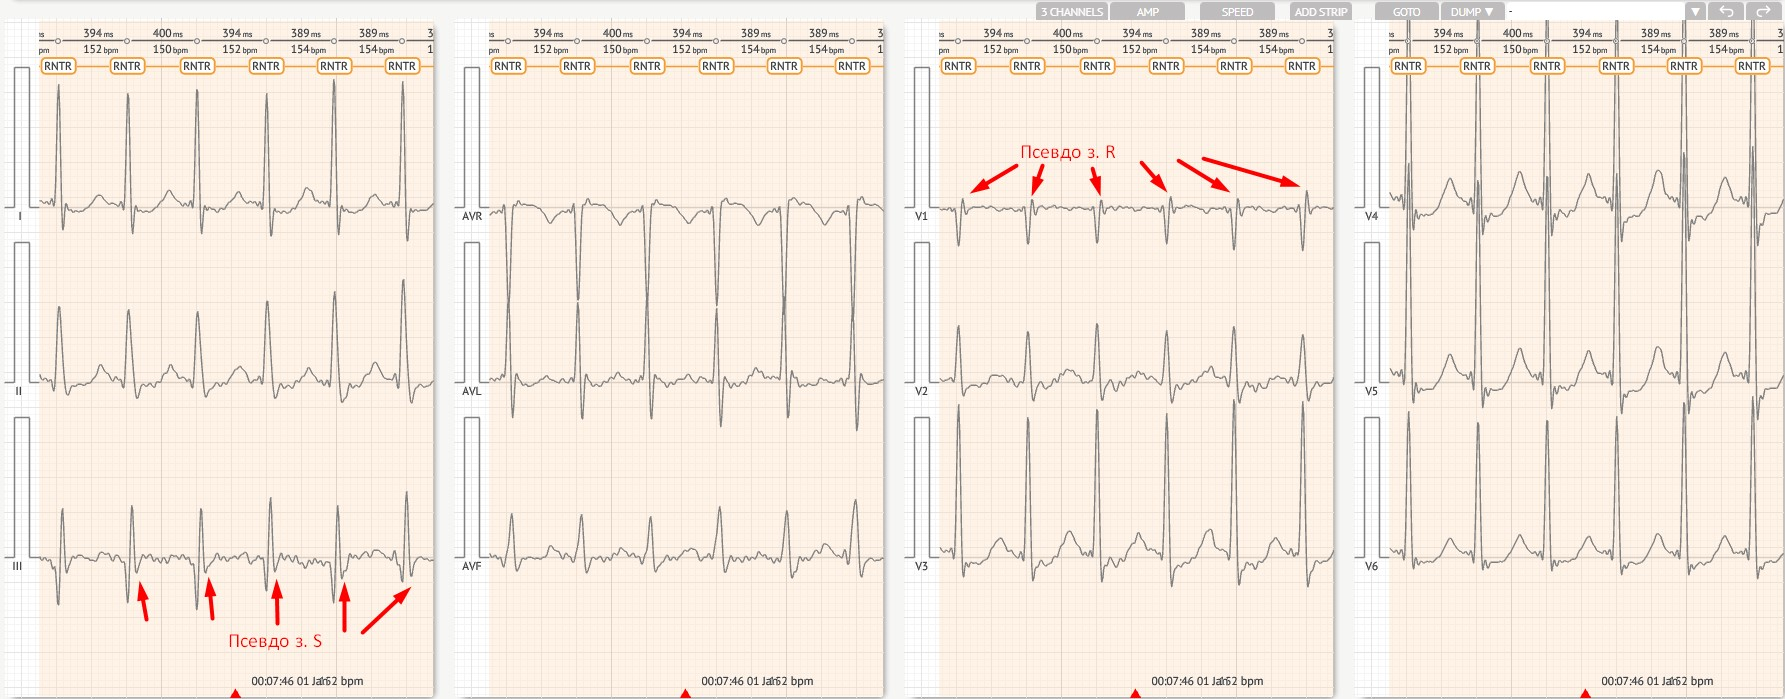

Суворо регулярний R-R, 140–250 уд./хв.

Нормальний комплекс QRS (якщо не виявлено аномалій).

Зубець P часто прихований або поблизу комплексу QRS; R-P \< 90 мс.

Ретроградна зубець Р, що з'являється після комплексу QRS.

R-P > 90 мс, але все ще \< P-R.